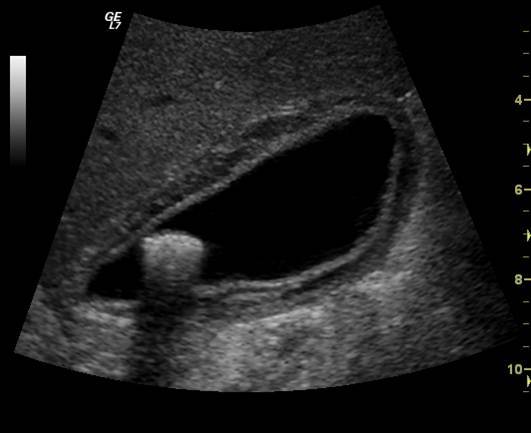

Tumefactive sludge

Sludge